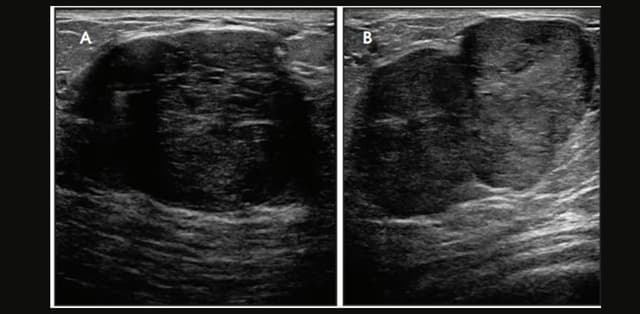

Nhân tuyến vú BIRADS 4 là gì? Cách điều trị

Nhân tuyến vú BIRADS 4 là một khái niệm còn khá mới mẻ. Không ít bệnh nhân cảm thấy hoang mang, lo lắng về mức độ nguy hiểm của loại u vú này. Vậy đây cụ thể là tình trạng như thế nào, hãy cùng TCI tìm hiểu. 1. Nhân tuyến vú BIRADS 4 là […]